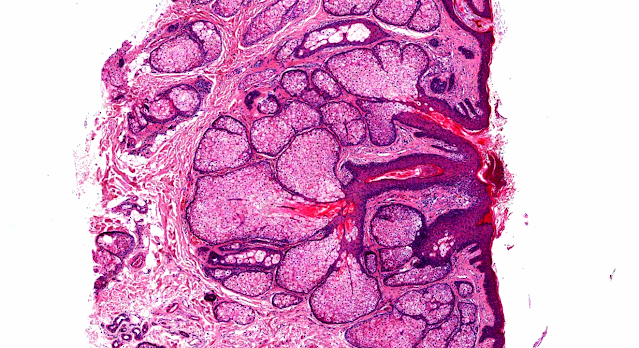

Answer of Dermatopathology Case 97

Follicular mucinosis is a tissue reaction pattern characterized by mucin deposition with follicular sebaceous units and is found as an idiopathic, primary, benign process (alopecia mucinosa), or as a secondary process due to inflammatory and neoplastic disorders (mycosis fungoides). When associated with follicular mucinosis, mycosis fungoides commonly pursues an aggressive course, often undergoing large-cell transformation, which is associated with resistance to therapy and poor prognosis. We present a case of mycosis fungoides with follicular mucinosis that was treated with incomplete courses of interferon, isotretinoin, and polychemotherapy with subsequent rapid progression to tumor-stage mycosis fungoides with large cell transformation and nodal and bone marrow involvement. In this setting, the patient was treated with local radiation therapy, total-skin electron beam therapy, and therapy and maintenance with the oral retinoid-X-receptor retinoid bexarotene, and achieved a durable complete remission.

Follicular mucinosis can occur as a primary idiopathic disorder or can arise in association with benign or malignant disease, most notably mycosis fungoides. We describe a patient with an aggressive folliculotropic variant of mycosis fungoides that initially presented as follicular mucinosis with alopecia. One month after the diagnosis of follicular mucinosis, a diagnosis of mycosis fungoides was made, and 3 months later inguinal lymph node involvement with mycosis fungoides developed. A skin biopsy specimen demonstrated prominent follicular mucinosis with folliculotropism of atypical cells and intrafollicular Pautrier's microabscesses. As demonstrated in this case, follicular mucinosis can be a presenting sign of rapidly progressive mycosis fungoides. In our review of follicular mucinosis and its association with mycosis fungoides, we found that the folliculotropic variant of mycosis fungoides appears more commonly to have an aggressive course than classic mycosis fungoides.